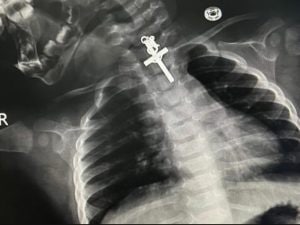

"Abbiamo dovuto aspettare 6 ore perché lo stomaco fosse vuoto visto che aveva bevuto il latte. Successivamente è stato effettuato il complesso intervento e tutto è andato molto bene" hanno spiegato i medici peruviani che hanno salvato la piccola.